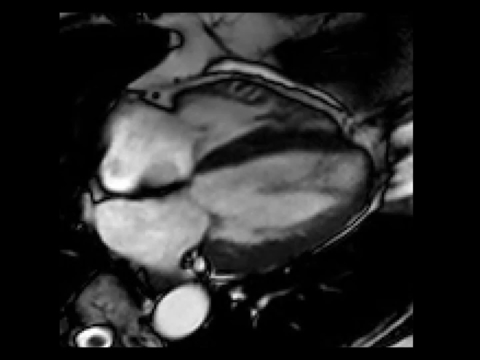

Vyšetření MRI srdce je bez známek edému myokardu a pozdního gadoliniového sycení (LGE) – nezjistilo tedy přítomnost zánětu, nekrózy, nahrazující fibrózy či infiltrace myokardu. Levá komora hodnocena při MRI jako mírně dilatovaná s EF 39 % (obrázek 2, video 4). Laboratorní vyšetření CK, LDH a železa, provedené k vyloučení dalších možných etiologií DKMP, bylo bez významné patologie, hodnota NT-pro BNP poklesla na 1 120 ng/ml.

Obr. 2. MRI srdce. 2A – nepřítomnost edému myokardu v T2 STIR TSE sekvenci v krátké ose, 2B – IR TFE sekvence v krátké ose – bez detekce pozdního sycení myokardu (LGE)

Video 4. MRI srdce, B-TFE sekvence v dlouhé ose – mírná dilatace a difúzní hypokineze stěn LK s EF 39 %

Na základě provedených vyšetření se domníváme, že etiologií srdečního selhání je u nemocné nejspíše dilatační kardiomyopatie na podkladě kardiotoxického postižení myokardu protinádorovou léčbou antracykliny – pozdní kardiotoxicita. Vzhledem ke zlepšující se systolické funkci LK s EF 39 % dle MRI jsme ustoupily od přístrojové léčby – implantace ICD.